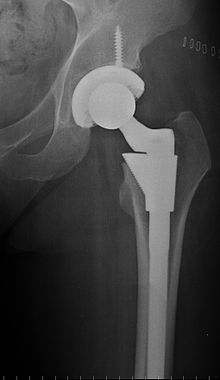

Just outside the operating room while I was waiting for my anesthetic, I overheard a critique of my surgeon crediting him with regularly performing 7 hip replacements in one day. From the tone of their voices, I took this to be high praise, but wasn’t sure if it was for speed, competency or both. As I understand it, the surgical process goes something like this. A deep 12 inch incision is made on the outside of the patients thigh, the surgeon reaches in, dislocates the hip, saws off the ball joint, hammers a metal spike into the femur, pops in the new ball joint and plastic liner and voila!

7. Twelve years ago I participated in a blind test of new orthopedic technology from Germany. At the time it was simply called “metal on metal” and the hip replacement patients were not told if they were receiving traditional replacements or the German “metal on metal”. I got the he German hip. If memory serves, my femoral stem was titanium and the rest, stainless steel. This time the stem was titanium, but unlike my first, it had holes which fostered more rapid bone adherence and growth.

* (Actually, the entire prosthesis is made of titanium which promotes bone adherence, and there are no wholes. The Femoral stern is fluted to prevent lateral twisting. Also, I have no screw in either replacement.)